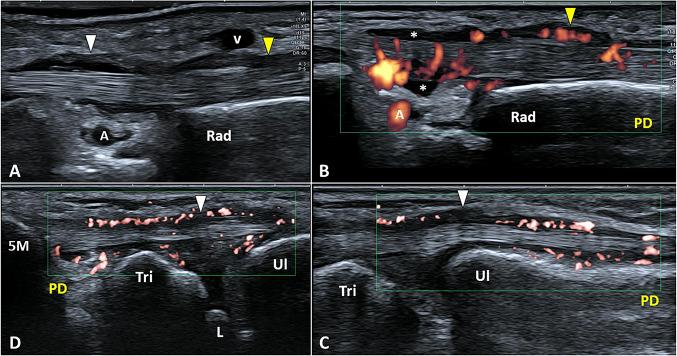

Padel is a racket sport, combining high-frequency and low-intensity athletic gestures, that has been gaining growing scientific interest in recent years. Musculoskeletal injuries are very common among padel players with an incidence rate of 3 per 1000 h of training and 8 per 1000 matches. To the best of our knowledge, a comprehensive collection describing the most common sonographic findings in padel players with musculoskeletal injuries is lacking in the pertinent literature. In this sense, starting from the biomechanical features of padel-specific gestures we have reported the ultrasonographic patterns of most frequent injuries involving the upper limb, the trunk, and the lower limb. Indeed, comprehensive knowledge of the biomechanical and clinical features of musculoskeletal injuries in padel is paramount to accurately perform a detailed ultrasound examination of the affected anatomical site. So, the present investigation aims to provide a practical guide, simple and ready-to-use in daily practice, to optimize the sonographic assessment of padel players by combining it with the clinical findings and the biomechanical features of athletic gestures.